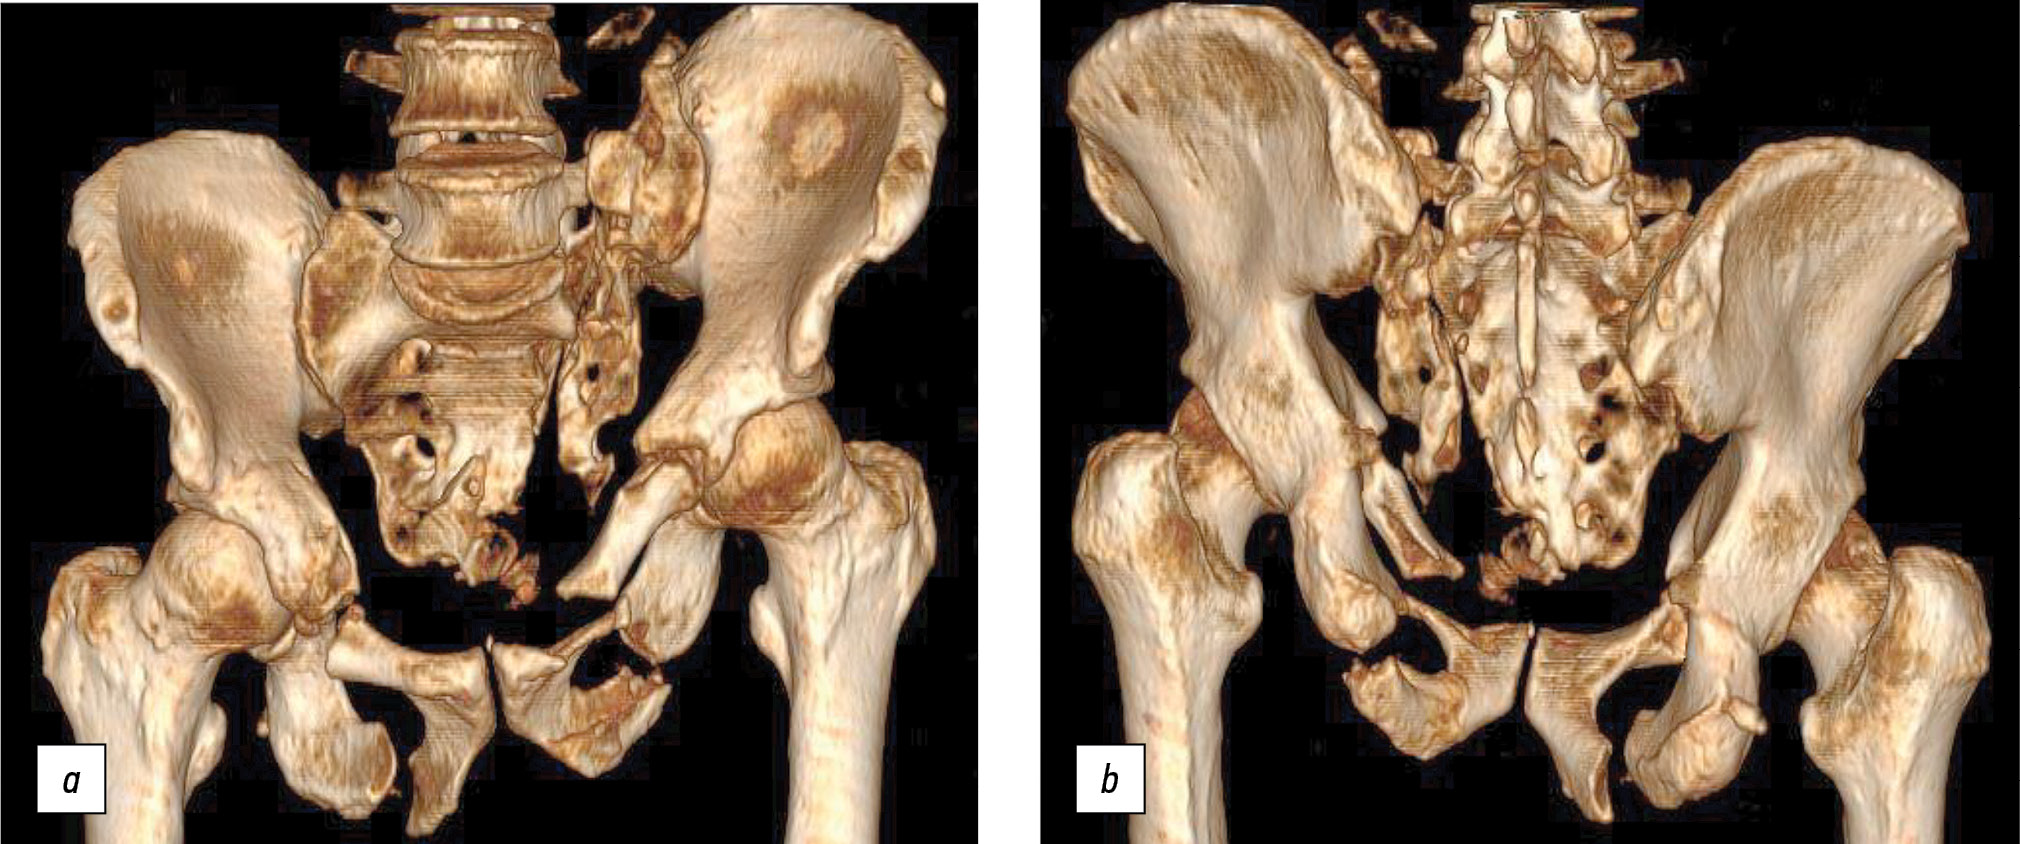

A patient aged 56 years presented 11 months after an injury (fall from the 5th floor). CT showed fractures of the pubis and ischium on both sides, and a longitudinal fracture of the lateral sacral masses on the left side in the Denis 2 area (Fig. 4).

Fig. 4. Computed tomography of the pelvic bones in 3D reconstruction mode: a — front view; b — back view.